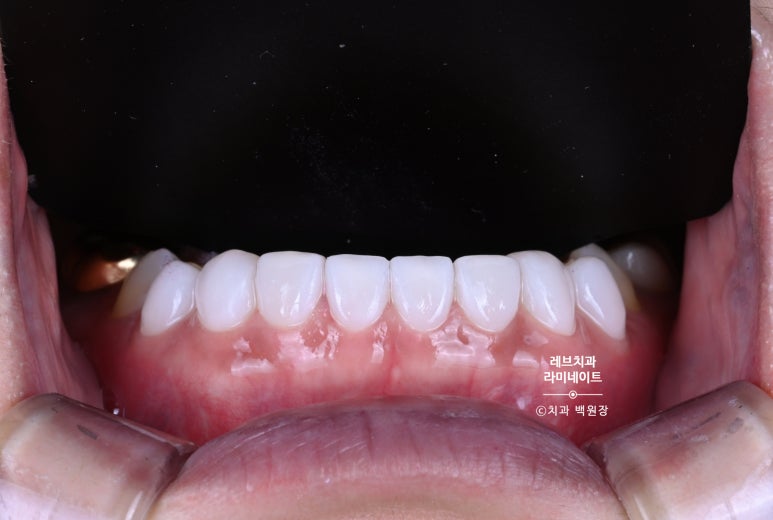

그렇게 해서 만들어온 레브네이트 베이직을 붙여드렸습니다.

치아가 조금 짧네? 라고 생각할 수 있습니다만, 위 치아의 모양과 환자의 외모를 고려한 치아 형태입니다.

더 길게했다면, 다른 치아들과 분위기가 잘 어울리지 않았을거에요.

그래서 이렇게 마무리 된 상황!!!

환자분이 너무 너무 만족해하셨고, 더 나아가 치아의 시림 없이 모양도 단정하고 보강된 치아를 만들어드릴 수 있어서 상당히 보람된 케이스였답니다.

Before & After

약간의 잇몸성형을 통해 아랫니가 조금 더 보이게 함으로써 자연스러움을 추가하였습니다.

그리고 위 치아와 아래 치아 색상의 조화를 이루어 깔끔한 이미지를 가지실 수 있게 도와드렸습니다.

아래 앞니의 경우 신경치료 추가 없이, 치아가 시리지 않는 선에서 최소 삭제로 치료해드렸습니다.

길이를 단정하게 맞추고, 색상을 개선하니 정말 20년은 젊어보이는 느낌이 들더라구요.

이제 아래앞니 색상 때문에 치아미백을 하지 않아도 된다고 좋아하셨습니다.